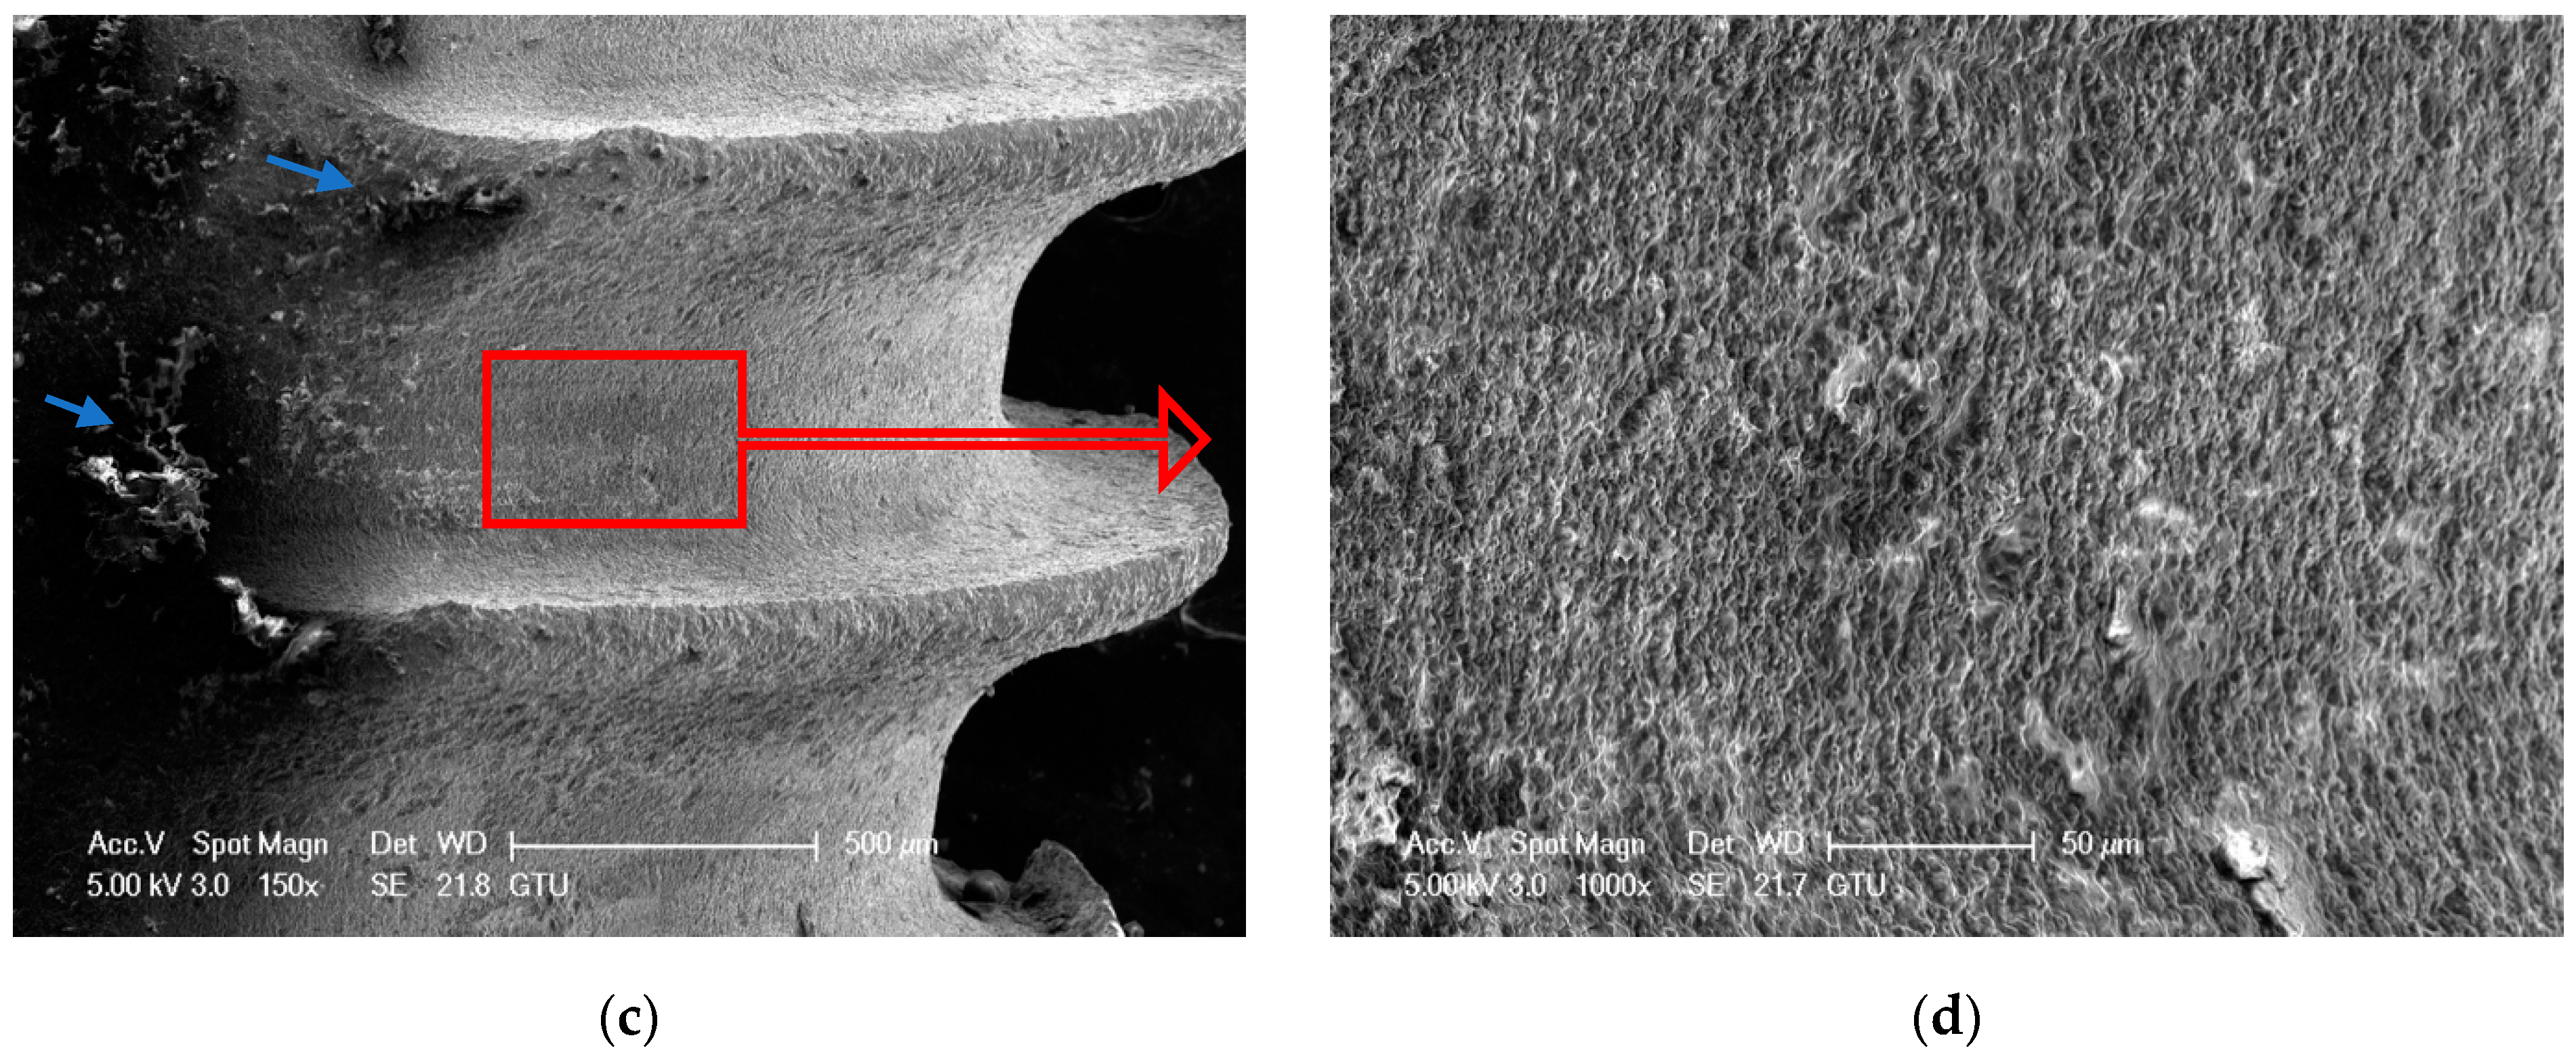

3.1. SEM Analysis

3.1.8. Control Group